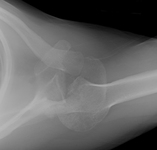

Lateral x-ray view of a posterolateral elbow dislocation

Personal collection of Dr Paul Novakovich